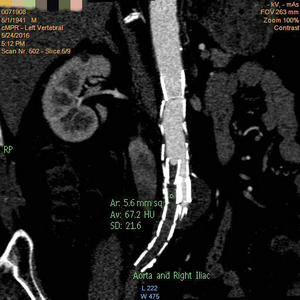

术前CTA提示腹主动脉支架右髂支闭塞